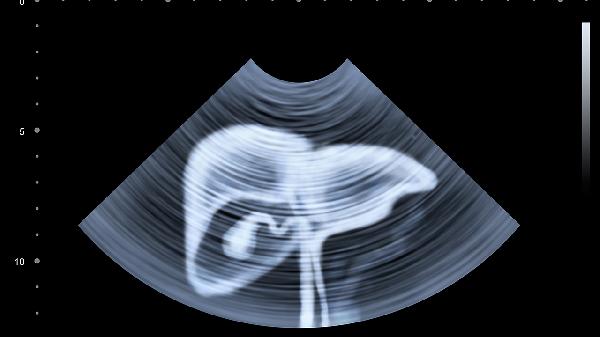

b超检查肝脏一般是准确的,可以用于筛查肝脏病变。肝脏b超主要通过声波反射判断肝脏形态结构异常,适用于脂肪肝、肝囊肿、肝血管瘤等常见疾病的初步诊断。

超声检查对体积较大的肝脏病变有较高检出率,如直径超过1厘米的占位性病变,典型表现为边界清晰的低回声或高回声区域。对于脂肪肝等弥漫性病变,b超可通过肝脏回声增强、深部衰减等特征进行判断,准确率较高。轻度脂肪肝患者检查中可能出现肝脏近场回声增强、远场回声减弱现象,中度以上脂肪肝可见肝内管道结构显示模糊。

部分情况下b超可能遗漏微小病灶或难以定性诊断。直径小于1厘米的病灶可能因超声波分辨力限制而显示不清,等回声结节与正常肝组织对比度低时容易漏诊。肝硬化早期某些纤维化改变在b超中表现不典型,需要结合瞬时弹性成像进一步评估。肝内胆管微小结石因声影不明显可能存在假阴性结果。

肝脏检查建议在空腹8小时后进行,以减少胃肠气体干扰。检查过程中可能需要配合吸气憋气等动作,使肝脏位置下移便于观察。发现异常回声区时可能需要结合甲胎蛋白检测或增强ct等进一步确诊,可疑恶性病变最终需通过病理活检明确性质。